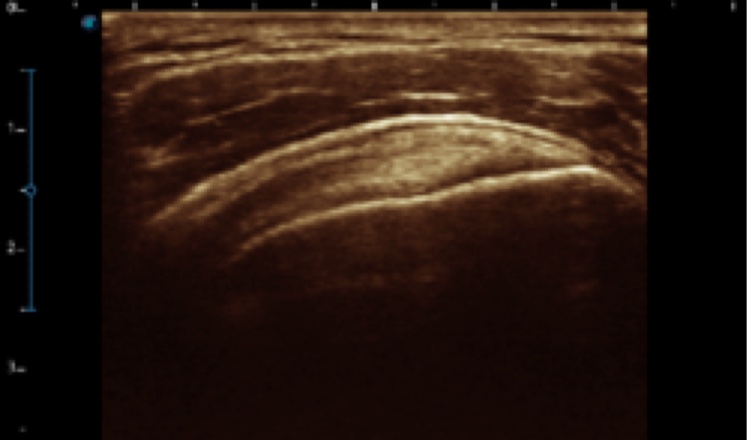

X5采用前端的超声专用芯片,将台式机大规模集成电路完美压缩在笔记本超声的精巧下,提高了系统的运算速度,加载μ-Scan微米成像、脉冲反相谐波等技术,带来优异的临床表现,清晰呈现高分辨率二维图像和层次丰富的血流图像